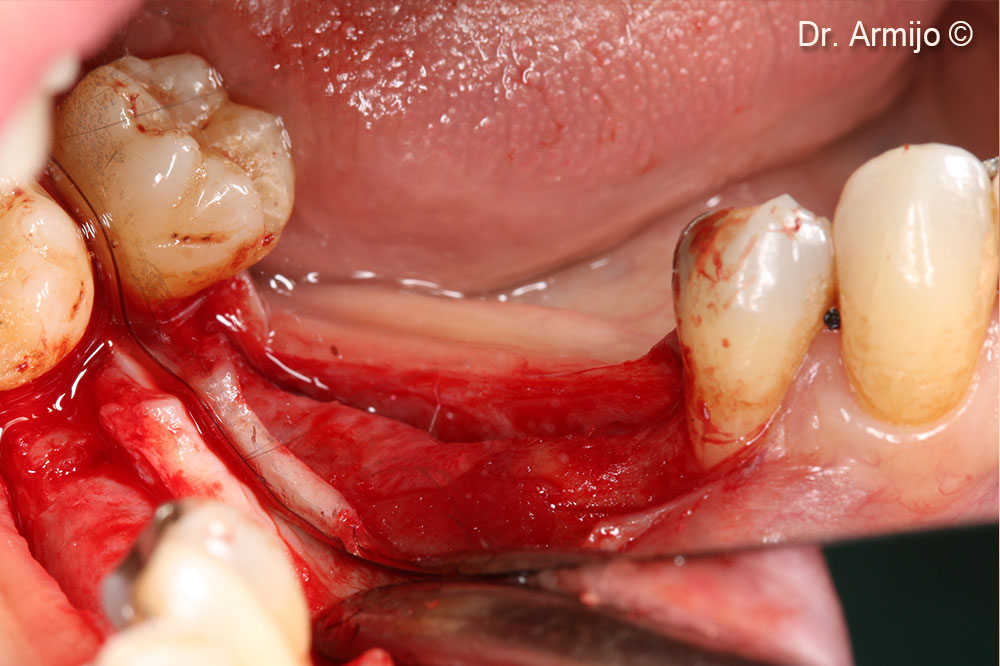

Detachment

Perforations down to the medullary bone.